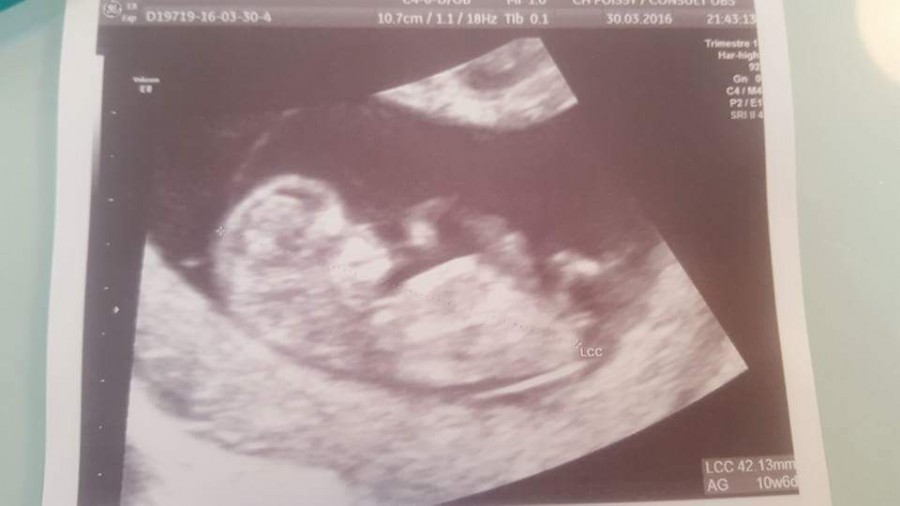

Sinon, pour l'écho, je voulais vous partager l'écho et savoir ce que vous pensiez du sexe du bébé, car avant de la faire, j'étais persuadée de ressentir que c'était une fille, ce que l'échographe m'a confirmé sans que je ne lui dise

(Même si on ne peut pas se fier à 100% à cette écho, 12+3)